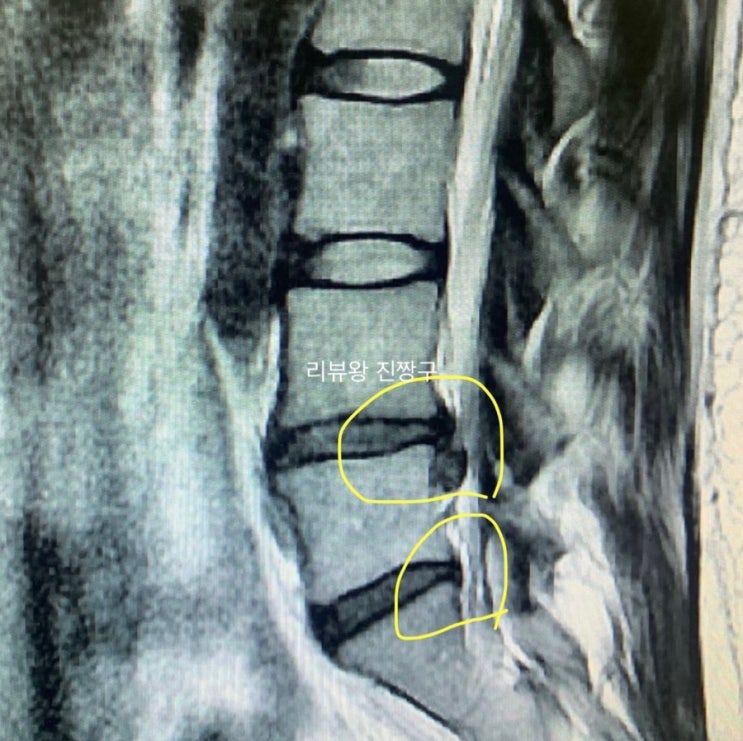

경험담) 허리디스크 터졌을 때 초기 대응, 운동 방법, 극복 기간

몇주 전 절친에게서 아는 지인이 허리디스크가 터져서 수술을 해야하는 상황이라고 연락이 왔었어요. 오늘...

경험담) 허리디스크 터지면 증상은 이렇습니다. (자세한 후기)

오늘은 저의 개인적 경험을 바탕으로 허리디스크가 터지면 어떤 증상이 나타나는지, 그리고 얼마나 고통스...